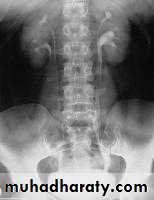

U/S: hydronephrosisIVU: diagnostic , hydronephrosis with fixed stenotic segment or complete obstruction

CT scan: hydronephrosis that ends abruptly